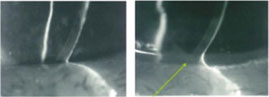

治疗方法:泪小(xiǎo)点栓塞的長(cháng)期疗效

术后泪河高度面由低变高了